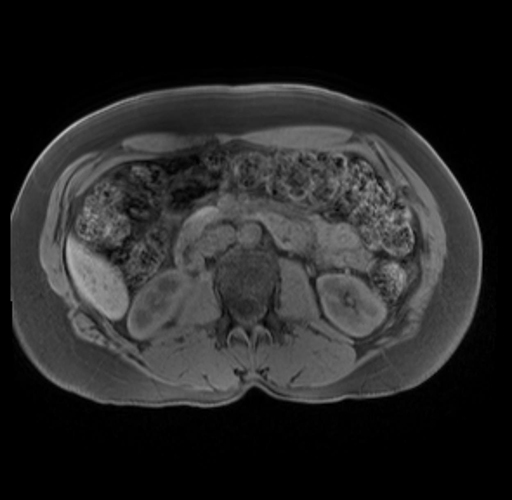

Imaging Analysis

Look through the patient's CT scan to identify any areas of concern for the necessary procedure.

Based on your CT findings, which issue(s) are present and would give reason for "planned slowing down moment(s)" in this case?